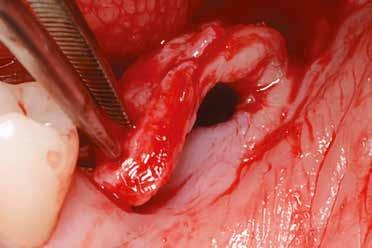

Szeretnék mutatni néhány ábrát az egyik bonyolult esetről, a közelmúltból. A CT-n látszik, hogy a három gyökér teljesen „körbenőtte” az ideget. Van olyan frontális metszeti kép, ahol csak a gyökerek vannak a nervus körül, ezen a szakaszon egyáltalán nincs meg a csontos fala a canalisnak. Szeparációs technikával, viszonylag könnyen, minimális traumával, szövődménymentesen sikerült eltávolítani a fog minden részét. A várakozásnak megfelelően, a beteg nem számolt be paraesthesiáról.

Alapos kivizsgálással, részletes tervezéssel, óvatos műtéti technikával még ilyen, extrém esetekben is sikeresen, szövődménymentesen meg lehet oldani a komplikált helyzeteket. Jobb lenne azonban, ha a műtét időpontjának helyes megválasztásával elkerülhetőek lennének ezek a magas rizikójú beavatkozások.